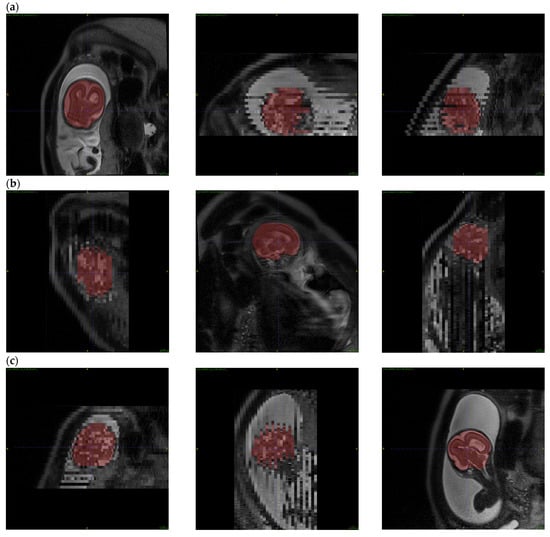

We have selected three axial series because the axial plane is also used to measure ventricles in clinical practice. Figure 4 shows the output of the reconstruction.

Figure 4. 3D Reconstruction: A Qualitative Comparison between Low-Resolution Input Data and High-Resolution Volumetric Reconstructions.